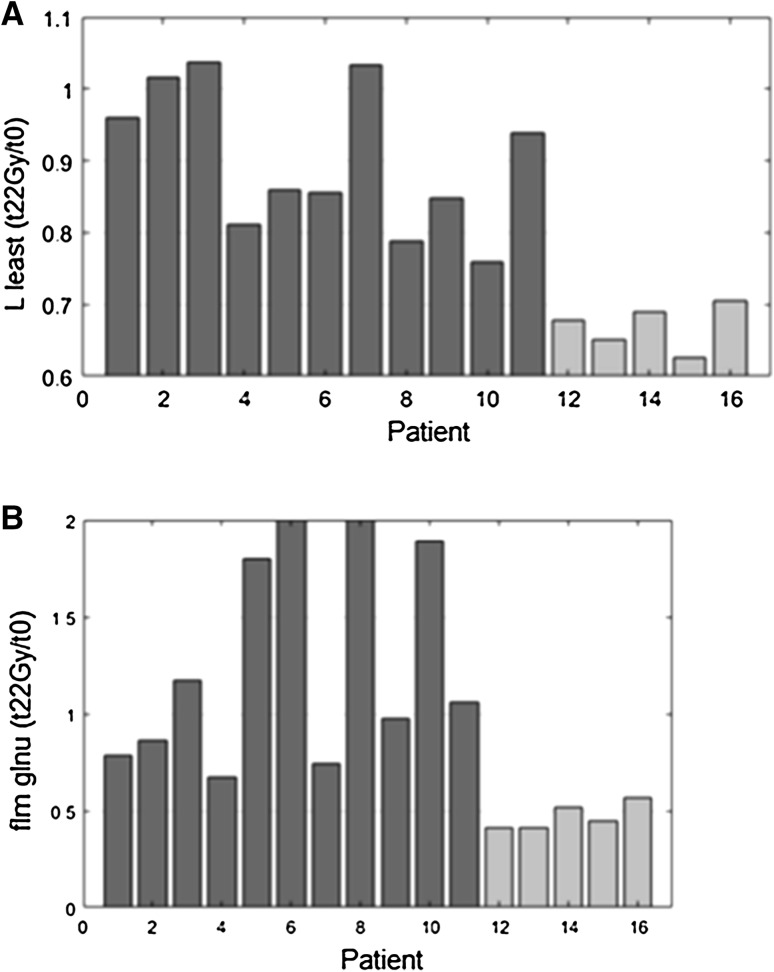

The most significant p values were observed for the L_least and glnu features (p value = 0.001), when their variation between the simulation imaging and the second treatment week t22 Gy MR was analysed.

Figure 2 shows the values of the two most significant aforementioned features for all the enrolled patients.

Fig. 2.

L least (a) and glnu (b) features trend. Patients undergoing cCR are indicated in light grey